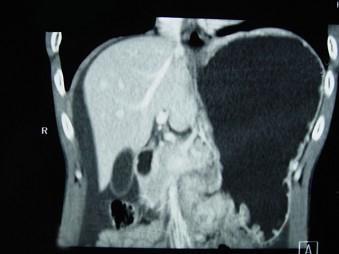

问题 男,65岁,中上腹痛腹胀、消瘦、乏力、纳差,影像检查如图,最可能的诊断是()

选项 A.胃间质瘤 B.萎缩性胃炎 C.肥厚性胃炎 D.胃窦癌 E.胃淋巴瘤

答案 D